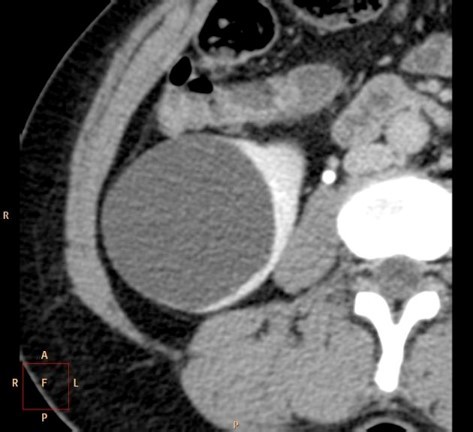

is this mass enhancing?

yes!

new finding. Management?

excise it